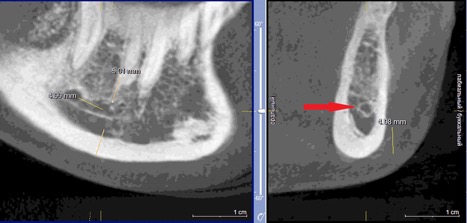

При измерении расстояния от резцовой петли до вестибулярной стенки нижней челюсти и её топографии в области правила «трёх пятёрок», выделено три положения канала, в котором проходит резцовая петля: канал прилежит, т.е. стенка канала образована кортикальной частью (рис 3), касается, т.е. имеет одну общую точку (рис 4) и не имеет общих точек.

Рисунок 3. КЛКТ Сагиттальный и коронарный реформаты переднего отдела нижней челюсти.

Стенка канала образована кортикальной частью кости.

Красная стрелка – «резцовая петля».

Красный пунктир – канал проходит в проекции участка правила «трёх пятёрок».

Рисунок 4. КЛКТ Сагиттальный и коронарный реформаты переднего отдела нижней челюсти.

Канал соприкасается с кортикальной частью кости (красная стрелка – резцовая петля).